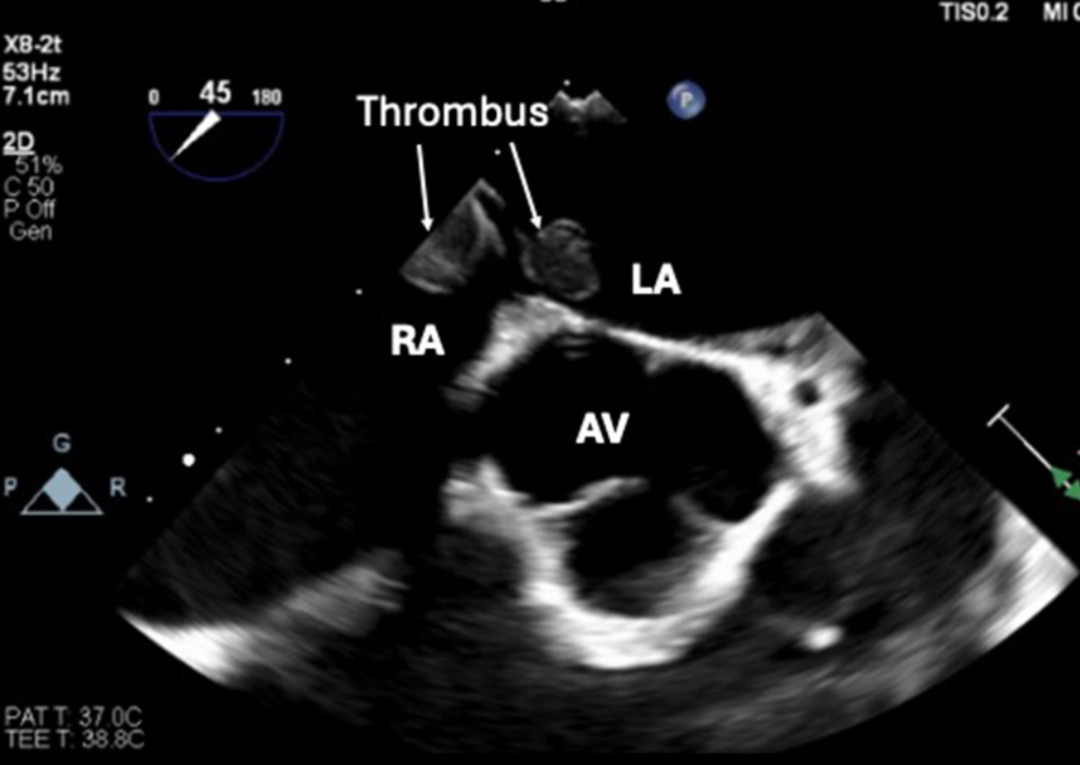

术中经食管超声心动图证实存在一个穿过PFO的大血栓(图 3、图 4)。患者随后接受急诊肺动脉取栓术+心房血栓清除术+PFO封堵术。

图 4 术中经食管超声心动图显示左心房和右心房内可见部分血栓(箭头)(RA:右房,LA:左房)。